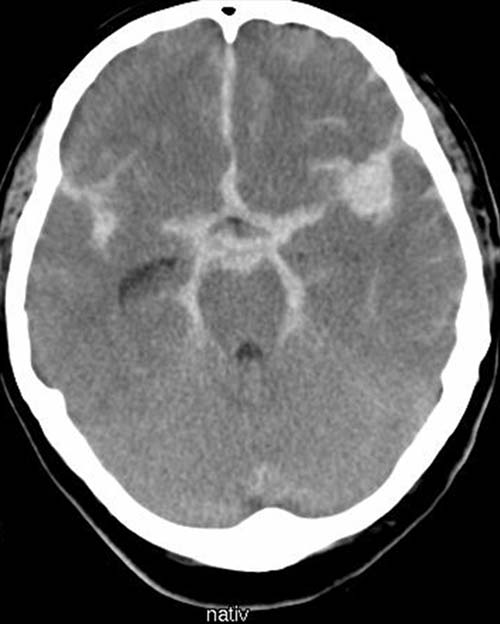

CCT nativ (ohne Kontrastmittel).

Hyperdense

(60-80 HE), verbreitete Darstellung des Subarachnoidalraumes.

Hyperdense (60-80 HE) Strukturen in den Hirnfurchen.

Schwellungszustand mit verstrichenen

Gyri und Sulci. Rundliche Hyperdensität in

der Sylvischen Fissur.

Akute Subarachnoidalblutung

mit Blutnachweis in

den basalen Zisternen und der Sylvischen Fissur beidseits.

Hirnödem.

V.a. Ruptur

eines A. cerebri media Aneurysma links

in der Sylvischen Furche.